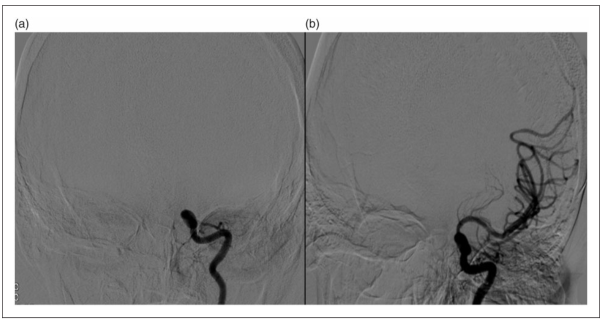

43岁女性,因急性右侧偏瘫及失语入院。CTA显示左侧颈内动脉(ICA)眼段完全闭塞。患者首先接受取栓治疗,取栓后在床突上眼动脉段可见约80%重度狭窄(图1(a))。用2×20 mm Coyote ES OTW球囊((Boston Scientific))扩张后获得了良好开通,没有残余狭窄(图1(b))。病人症状良好,出院时服用波立维和阿司匹林,没有出现并发症。

图1